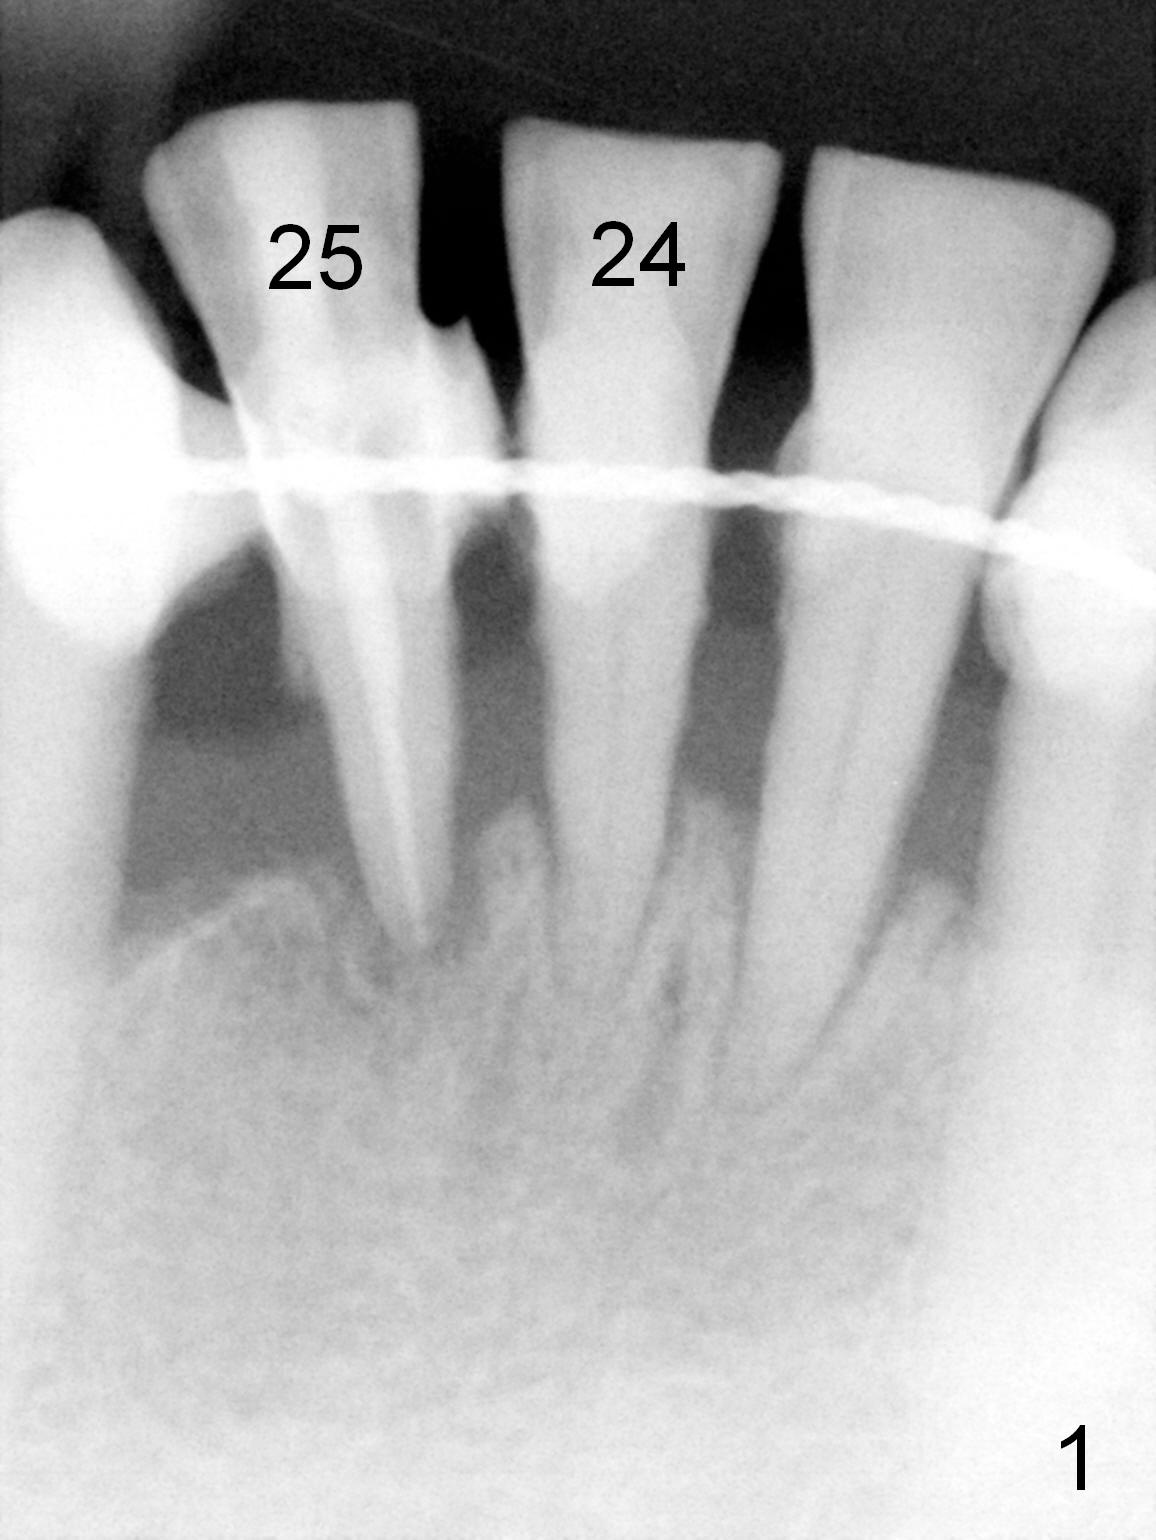

A 59-year-old man requests a partial denture after loss of #24 and 25, seven years after splintng (Fig.1,2). The remaining incisor (tooth #23) has mobility II. After discussion, he agrees with implant-supported FPD. Two of 1-piece implants will be placed at #23 and 25 (Fig.2) to avoid too-close complication. The first implant will be placed at #25. The socket of #23 will be treated with Clindamycin. Surgical and restorative stents are to be fabricated from the model made 7 year earlier (in the shelf of the lab). Use a 3x14 mm dummy implant for trajectory determination. Also prepare angled implants.